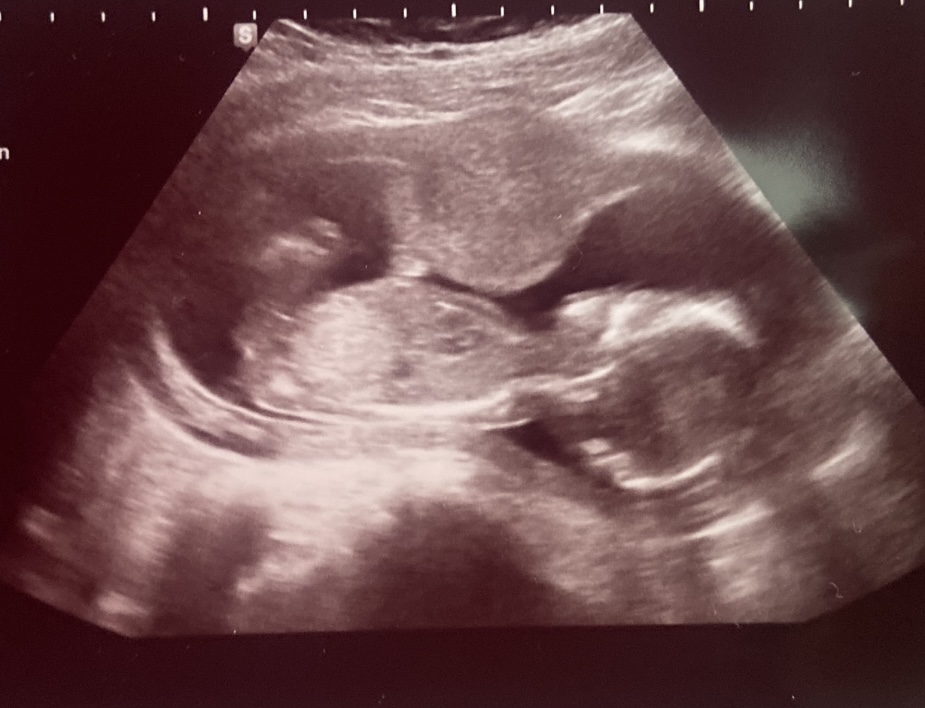

Určitě tě nemine 3D ultrazvuk.